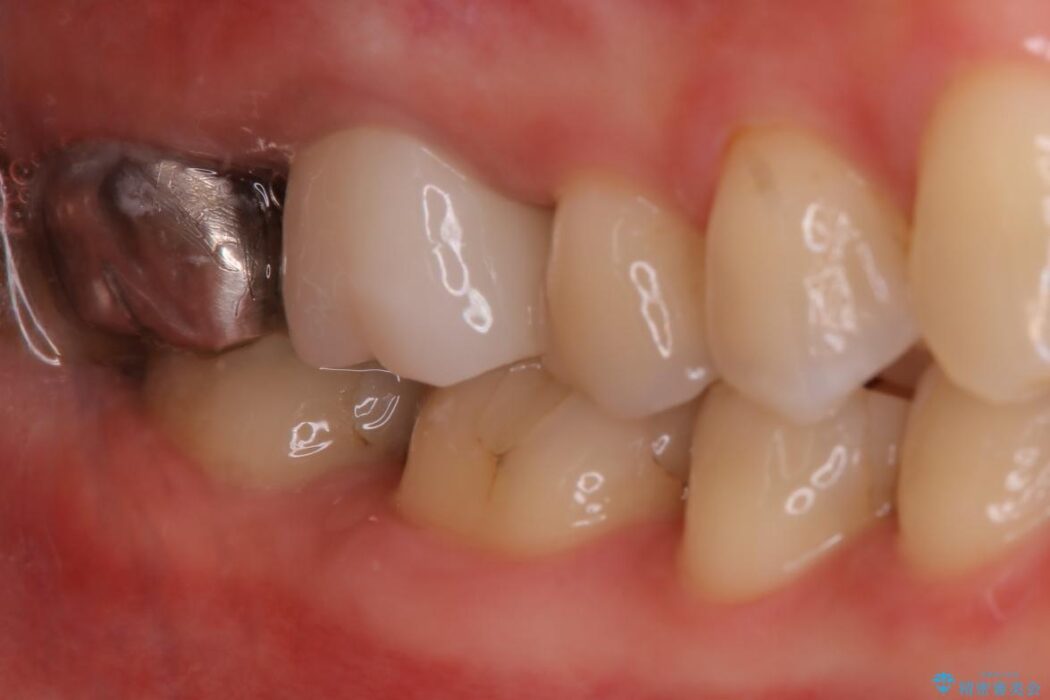

別の部位の治療で通われていた患者様ですが、歯ぐきにできものが繰り返しできるとのことで相談されました。

X線画像を診断すると、充填不良の根管の先に透過像が認められたため、再根管治療をご提案いたしました。

根管治療を再度行うことでフィステル(ニキビのようなできもの)は消失しました。

最終的にセラミッククラウンによる補綴治療を行いました。